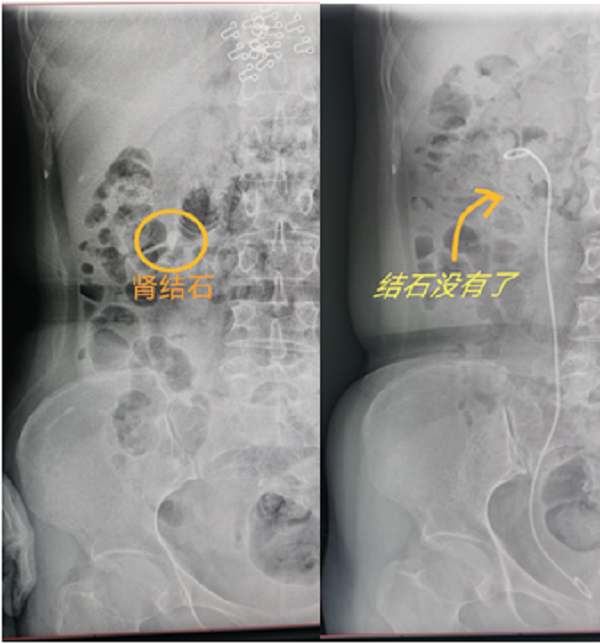

65岁杨大姐和50岁的潘大姐就是这种手术的受益者,她俩均因为腰痛来我院泌尿外科门诊咨询就诊,医生诊断为肾结石,并建议她们做输尿管软镜手术治疗,通过医生的详细介绍,杨大姐和潘大姐对这种没有任何刀口的手术方式表示很惊讶,紧张的心情一下子就放松了。

通过应用负压吸引鞘,主任医师辛明辉、副主任医师刘伟带领泌尿外科团队在麻醉医师的通力合作下,对结石进行了完全清除,手术均顺利完成。经过术后康复,杨大姐和潘大姐在手术后第三天就顺利出院了。